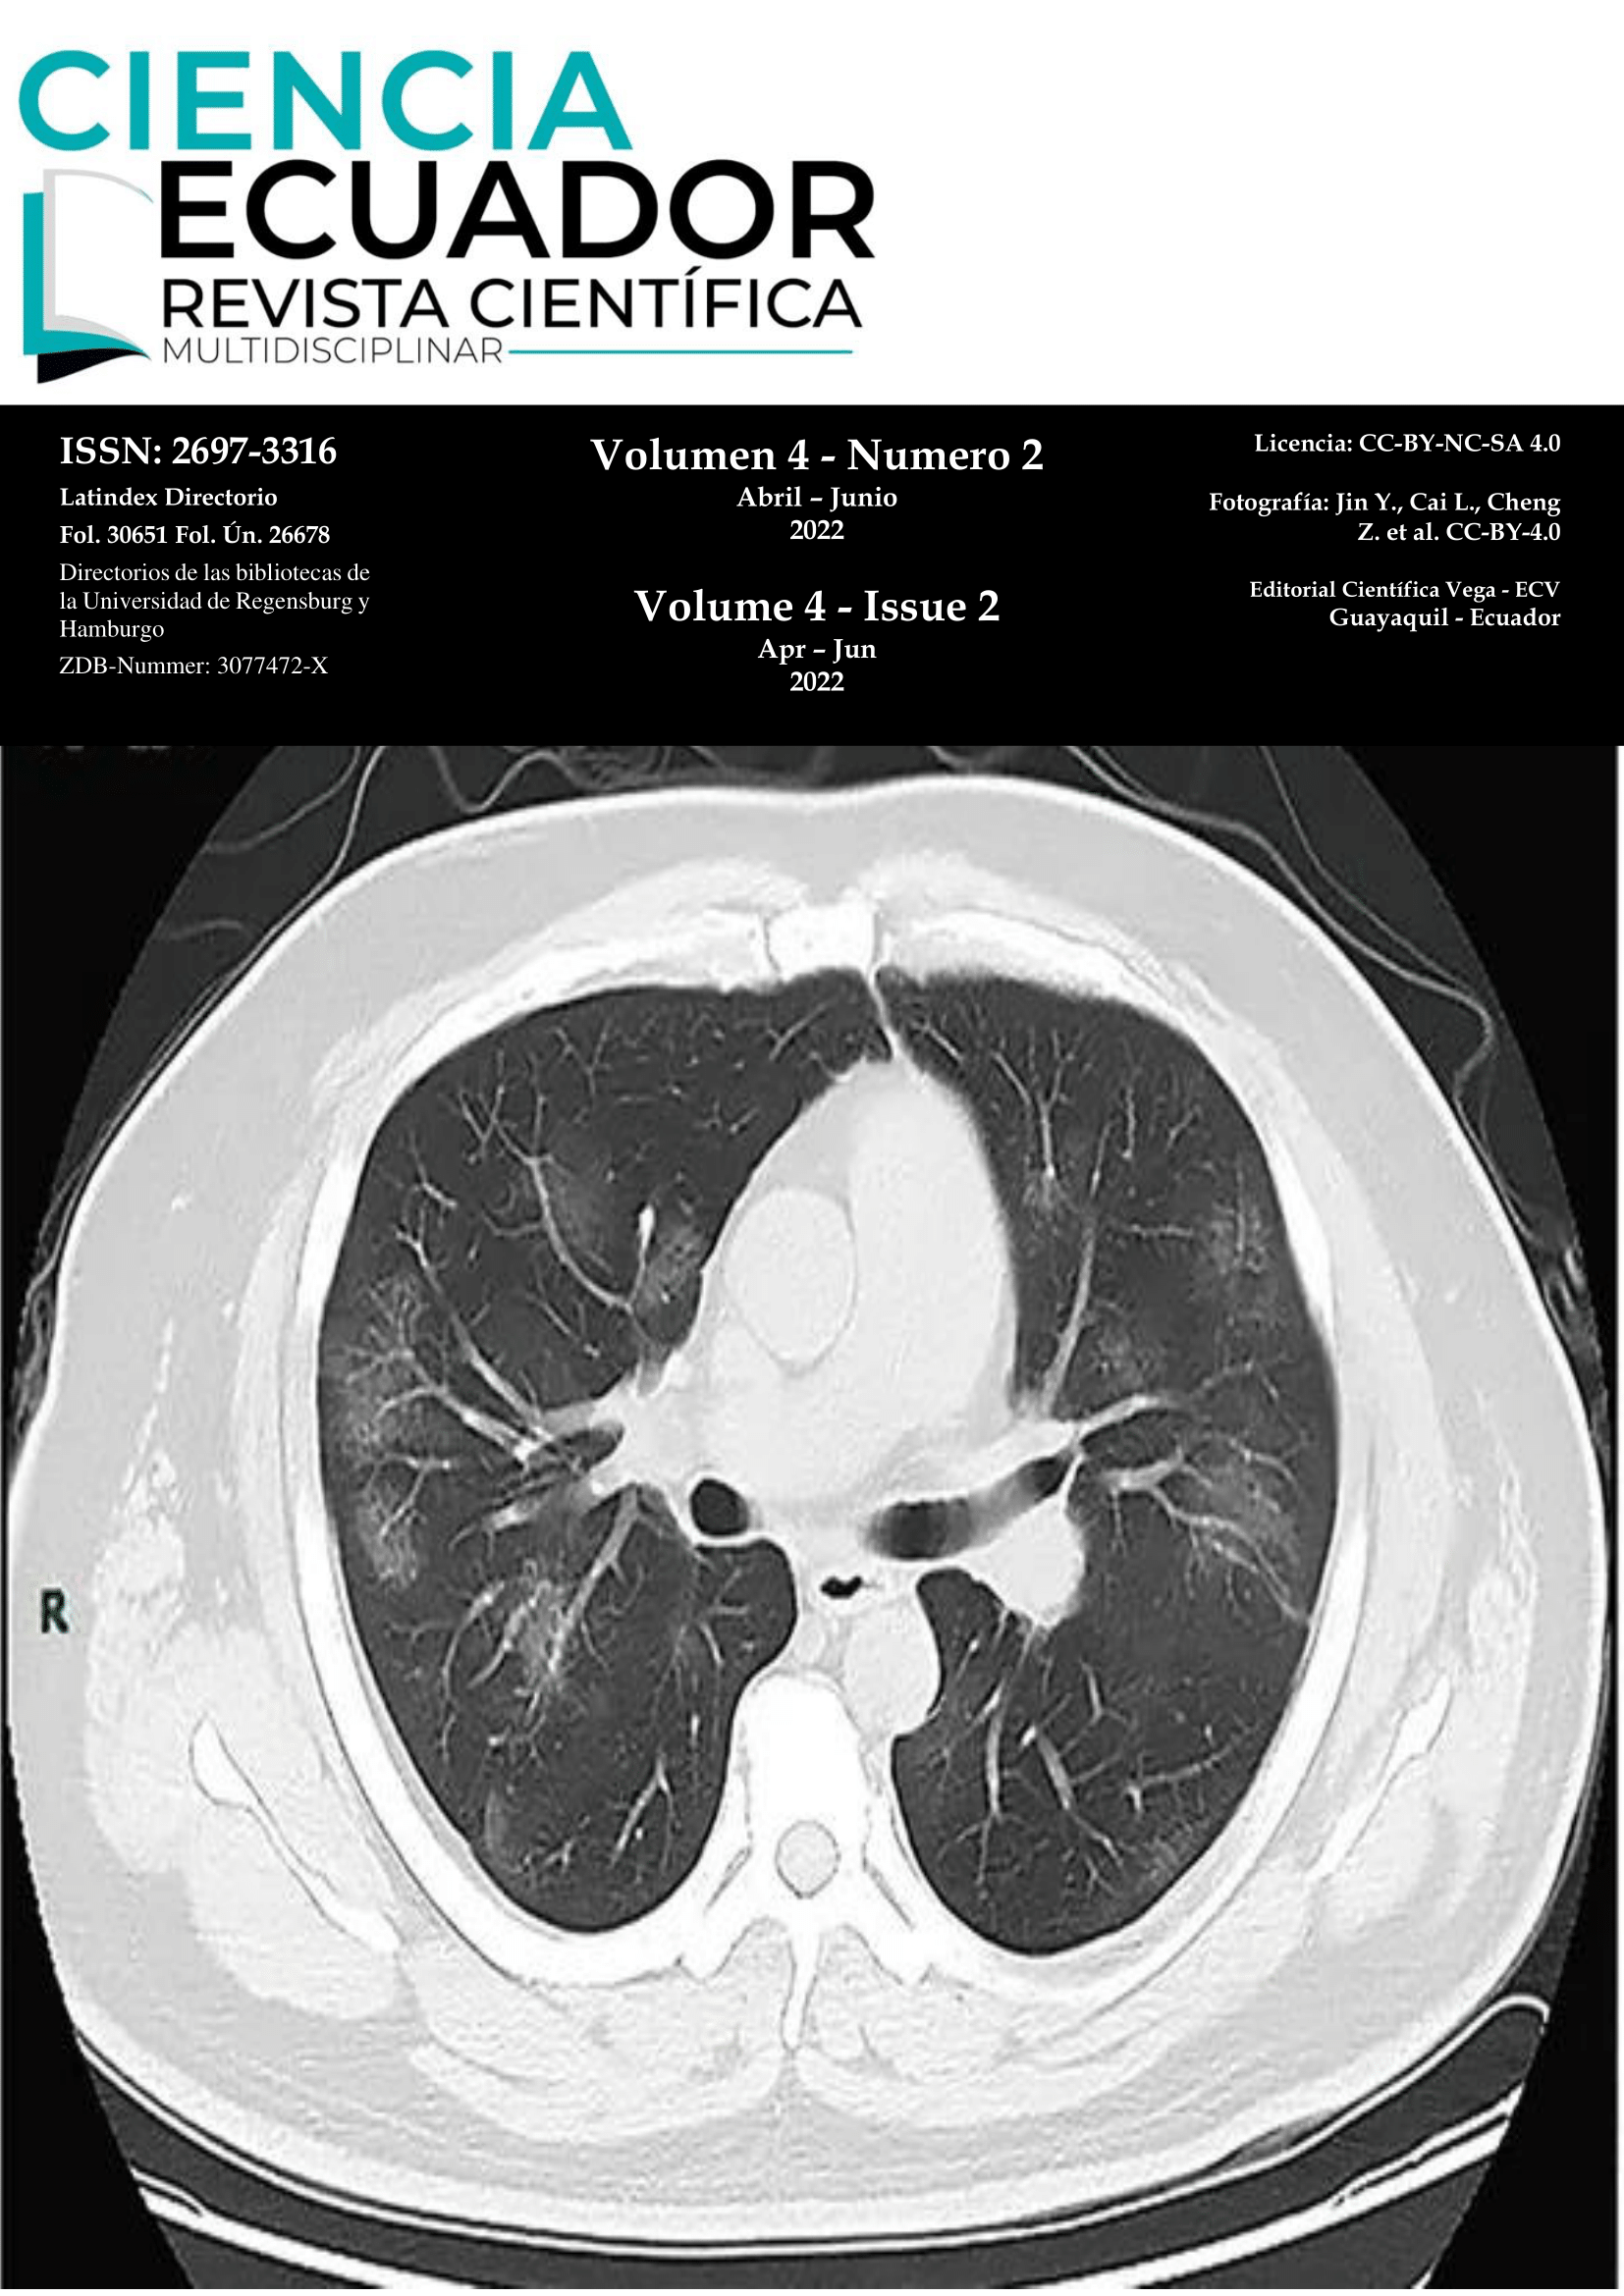

Vol. 4 Núm. 2 (2022): COVID-19

En el presente número presentamos casos de COVID-19.

Evolución tomográfica de paciente con COVID-19

Imagen Médica

Harold Reynaldo Farfán Cano, Stanley Farfán Cano, MD. Mprof., Dr. Richard Bonilla Crespín